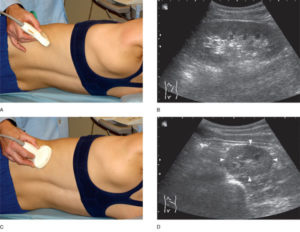

Как проходит обследование

Исследование проводится в положении сидя или лежа на боку. На кожу в области поясницы врач-сонолог нанесет специальный гель, обеспечивающий тесный контакт между кожным покровом и датчиком прибора. Затем доктор будет перемещать над исследуемой областью ультразвуковой датчик, одновременно с этим рассматривая на мониторе постоянно изменяющиеся изображения («срезы»).

Методика проведения

Когда выполняется доплерография сосудов почек, пациент находится в лежачем положении, методика проведения ничем не отличается от того, как делают обыкновенное УЗИ. Врач проводит смазанным гелем датчиком по коже. На экране монитора появляется изображение изучаемого участка. Доплеровское исследование сосудов почек занимает всего полчаса, а результаты специалист получает сразу.

Как выполняется УЗИ

Проводится обследование в горизонтальном положении. Также диагностика может осуществляться в сидячем состоянии. Процедура безболезненна и отнимает около получаса. УЗДГ полностью безопасна.

Врач при проведении УЗИ внимательно изучает состояние органа

Пациент при обследовании находится на медицинской кушетке. На исследуемую область наносится специальный акустический гель, который направлен на улучшение скольжения и визуализации. От аппарата исходят ультразвуковые волны, которые в дальнейшем трансформируются в электроимпульсы.

Полученные данные отражаются на мониторе. При обследовании отсутствует дискомфортное ощущение. УЗДГ сопровождается негромкими ритмичными звуками. Такой шум является нормой и не должен провоцировать беспокойство.

Во время процедуры больной ложится на кушетку, врач прикладывает к коже живота уз датчик, смазанный гелем и поворачивая его под разными углами, получает изображение почек и сосудов в разных проекциях, которое выводится на монитор.

Техника исследования

Как было выше сказано, проведение ультразвуковой диагностики запрещено после колоноскопии, ирригоскопии и фиброгастроскопии, так как вывести на экран более точные изображения не удается. Пациент при обследовании должен занять лежачую или сидячую позицию.

Специалист наносит специальный проводящий гель на область поясничного отдела для удобства и легкого скольжения датчика по кожным покровам. Затем врач направляет прибор в разные стороны для проверки состояния кровеносных сосудов. Полученные изображения можно увидеть на мониторе.

Эта методика обследования совершенно безопасная и безболезненная. Максимальная длительность процедуры не превышает более 30 минут. После прохождения диагностики специалист отдает полученные показатели, с которыми нужно обратиться к лечащему врачу для расшифровки.